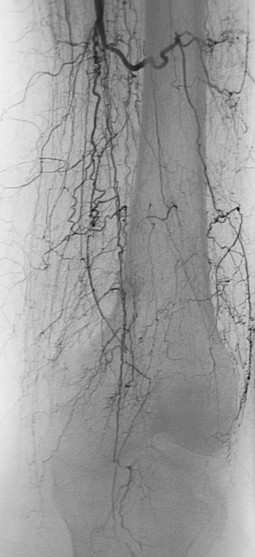

Deutsch Auch Morbus WiniwarterBuerger oder WiniwarterBuergerSyndrom Endangiitis obliterans Krankheit Medium hochladen Wikipedia Ist ein(e) Krankheit, designated intractable/rare diseases Unterklasse von arterial occlusive disease, predominantly mediumvessel vasculitis, secondary glomerular disease Benannt nach. Ischämie» die Differentialdiagnose eines Morbus WiniwarterBuerger erwogen Die selektive Angiographie vom zeigte die typischen «KorkenzieherKollateralen» am rechten Unterschenkel (Abb 1 x) Eine Ilomedintherapie war allerdings nicht erfolgreich, so dass am 1302 eine Grosszehenamputation rechts durchgeführt werden musste. Synonyme Morbus WiniwarterBuerger, VonWiniwarterBuergerKrankheit, Endarteriitis obliterans, Thrombangiitis obliterans Englisch endangitis obliterans, Buerger's disease Inhaltsverzeichnis.

Buerger related the cellular nature of arterial thrombosis, as had von Winiwarter, and described the absence of large vessel involvement It was Buerger who named the disorder “thromboangiitis obliterans”, and only briefly mentioned its relationship with smoking In 1924, Buerger reported that tobacco use was probably a predisposing factor 2. Morbus WiniwarterBuerger Stuttgart, Germany Georg Thieme;. Ischämie» die Differentialdiagnose eines Morbus WiniwarterBuerger erwogen Die selektive Angiographie vom zeigte die typischen «KorkenzieherKollateralen» am rechten Unterschenkel (Abb 1 x) Eine Ilomedintherapie war allerdings nicht erfolgreich, so dass am 1302 eine Grosszehenamputation rechts durchgeführt werden musste.